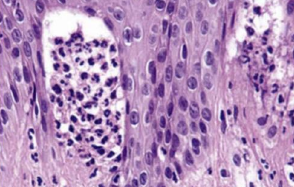

• hyperparakeratosis, acanthosis

• upper spinous layer 局部角化

• ell-within-a- cell